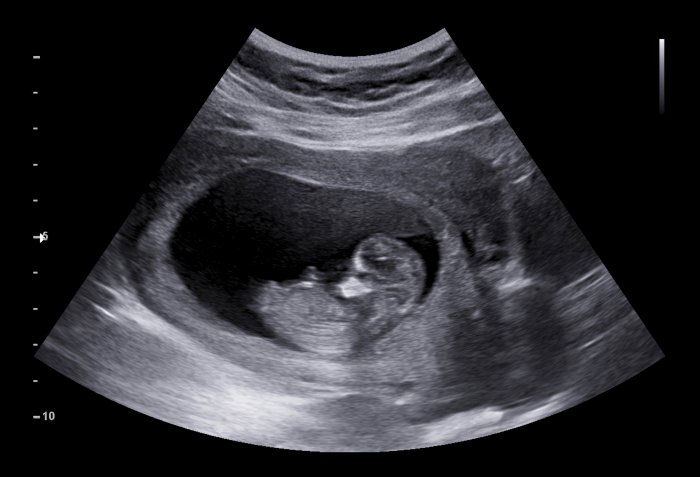

怀孕分很多阶段,大家比较熟悉的是孕“早中晚”期。实际上,还有一个阶段不常被提起,对胎儿和孕妇都是至关重要的。...

怀孕分很多阶段,大家比较熟悉的是孕“早中晚”期。实际上,还有一个阶段不常被提起,对胎儿和孕妇都是至关重要的。